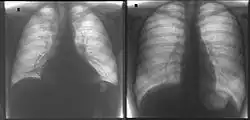

Bildgebung

Im Röntgen-Thorax ist der Herzschatten verbreitert. In der Echokardiographie und in der Kernspintomographie sieht man eine Erweiterung der Ventrikel und der Vorhöfe. Die Wand des linken Ventrikels ist meist verdünnt, der linke Ventrikel kugelig umgeformt und allseits vermindert beweglich (kontraktil).

Die Auswurffraktion ist reduziert. Der Abstand zwischen vorderem Mitralsegel und Septum ist vergrößert. Oft liegen eine Mitralklappeninsuffizienz und eine Trikuspidalklappeninsuffizienz vor.